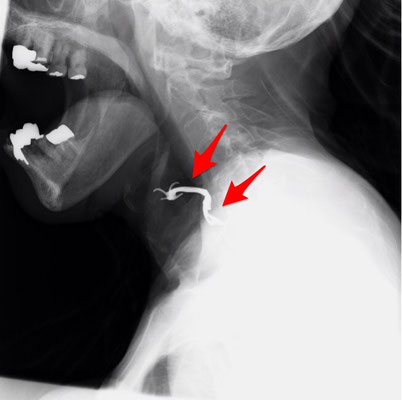

下のような、固定するための長い足を持った義歯は、縦向きに飲み込んでしまいがちです。爪の部分が、粘膜に食い込み、口からの摘出がかなり困難かつ、粘膜損傷の危険を伴います。

このケースは、頸部の皮膚を切開し、咽頭や食道の粘膜を切開の上、外側から摘出されました。